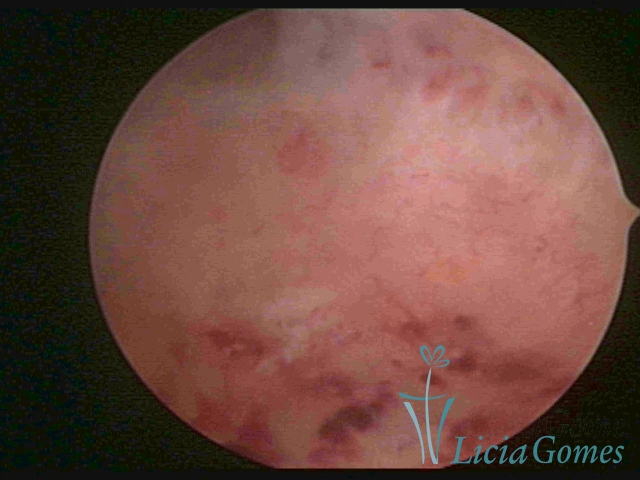

ENDOMETRITE CRÔNICA

A superfície do endométrio pode exibir alterações como um pontilhado vermelho formando novelos vasculares, o endométrio liso e hiper-vascularizado, ou com áreas vermelhas de forma intensa, com limites precisos e pontilhados branco amarelados no seu interior dando um aspecto “CASCA DE MORANGO” e uma coloração amarela pálida das comissuras fúndicas e laterais, em contraste com o vermelho intenso das paredes.

Já na Endometrite crônica avançada visualiza-se um endométrio delgado, com áreas desnudas, às vezes, ulcerada, com uma coloração cinza esverdeada com micro varizes, de coloração mais acastanhada, mais acentuada nas regiões cornuais (distrofia vascular).